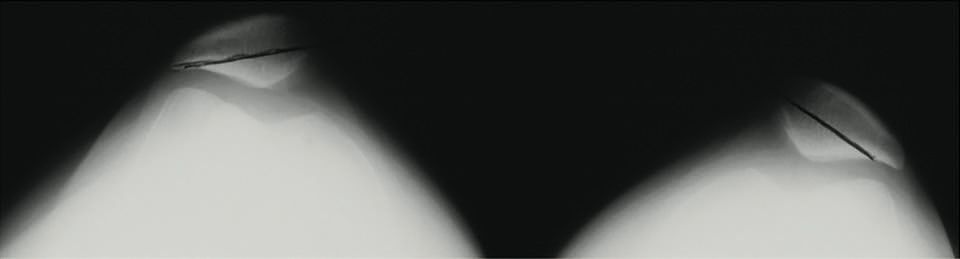

Technique Greffe courte du LCA : Technique Dehors-dedans avec tunnels complets , Jean-Claude Panisset Clinique des Cèdres, Echirolles, France , Johannes Barth Clinique des Cèdres, 38130 Echirolles, France N°256 Cahier 1 - Août/Septembre 2016 ● 9 min de lecture